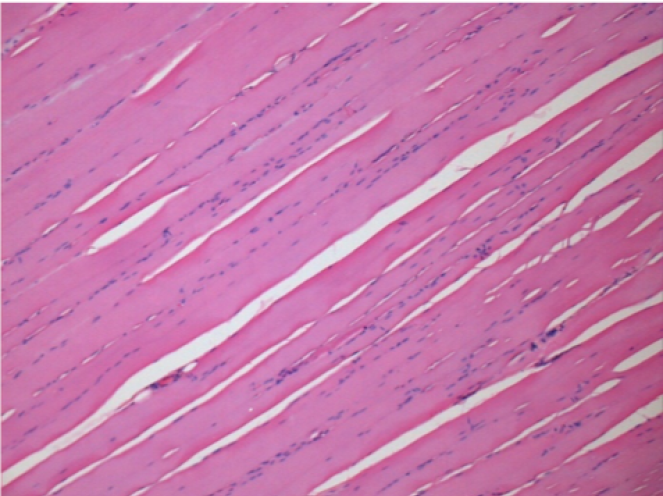

7 months after Endopeel Injection

7 months (D210)after Endopeel IM Injection 0.1ml in the right pretibial muscle.

Complete Restitutio ad integrum after 7 months

L : Control-100xD210

R:100xD210

L :Control 50xD210

R50X-D210